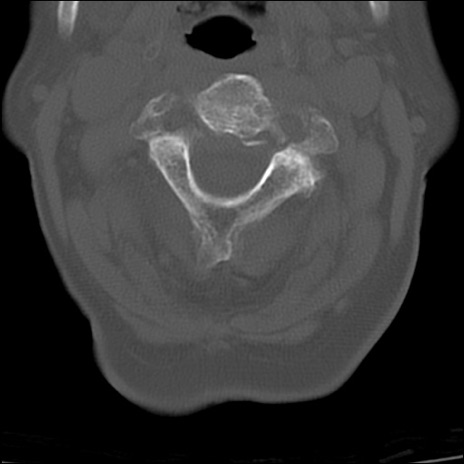

頚椎CT

矢状断像